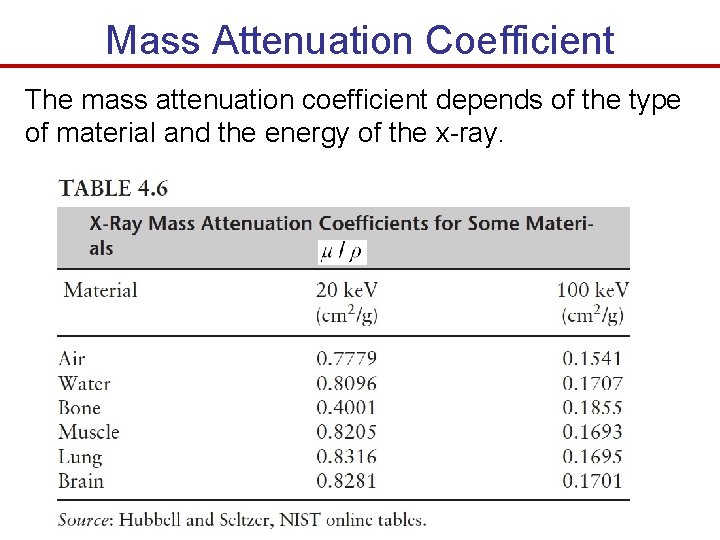

Mass Attenuation Coefficient The mass attenuation coefficient depends of the type of material and the energy of the x-ray.